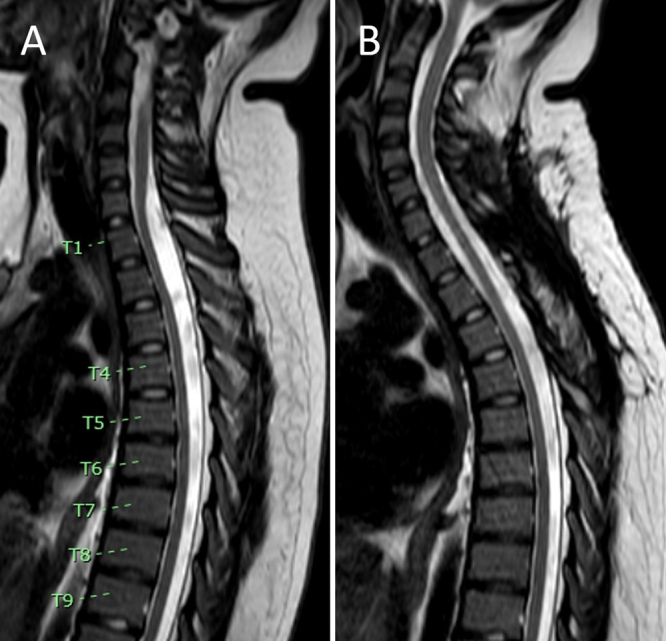

Background: Spinal arachnoid cysts can cause myelopathy through spinal cord compression. While MRI is the standard for diagnosis, traditional sequences may not clearly define cyst borders and septations, which are important for guiding surgical intervention. Balanced fast field echo (B-FFE) is an MRI sequence that highlights small arachnoid membranes within and at the borders of CSF spaces.

Observations: The authors report the case of a 13-year-old female who presented with progressive lower extremity paresthesias and weakness and urinary incontinence. MRI revealed an intradural cervicothoracic arachnoid cyst (C7-T3) dorsal to the spinal cord. B-FFE was used to identify the upper and lower borders of the intradural arachnoid cyst and its internal septations. These findings corresponded precisely with intraoperative findings and guided fenestration at the cyst's cranial, caudal, and internal septal ends. Postoperatively, the patient's symptoms resolved, and MRI confirmed the resolution of mass effect. At the 10- and 30-month follow-ups, there was no evidence of cyst recurrence clinically or radiographically.